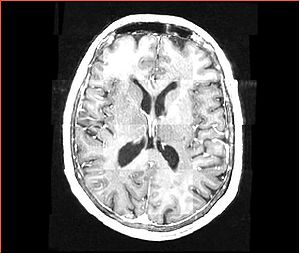

Data

• Input images: isotropic post-contrast T1 MRI acquired at different locations of BWH during 2006-2008, used under medical records study IRB. Time period between acquisition of scans for each patient is about 1 year.

• images were acquired with the same sequence, but possible on different scanners, all scans are axial